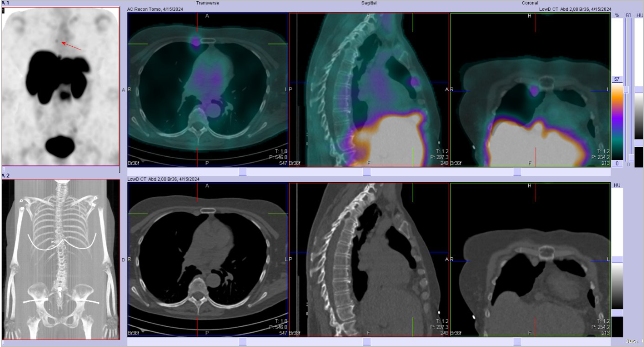

Scintigrafie Octreoscanem

I. v. jsme aplikovali 190 MBq analogu somatostatinu značeného 111In

(přípravek OctreoScan firmy Curium Netherlands B.V.) a provedli pomocí hybridní tomografické scintilační kamery Symbia T2 firmy Siemens opatřené kolimátory pro střední energie planární celotělovou scintigrafii a cílenou tomografickou scintigrafii (SPECT) břicha a pánve kombinovanou s CT.

/ Obr. č. 1: Celotělová scintigrafie v přední a zadní projekci 4 (vlevo) a 24 hod. (vpravo) po aplikaci OctreoScanu.

/

Pozorujeme patologické ložisko zvýšené depozice radiofarmaka v segmentu S4 pravého jaterního laloku, ve dvou uzlinách – jedné nad bránicí a druhé pod levým jaterním lalokem a v pánvi na rozhraní levé kosti kyčelní a kosti křížové, nález svědčí pro tkáň se zvýšenou denzitou somatostatinových receptorů.

Závěr:

U 68leté ženy s neuroendokrinním tumorem nejasného primárního zdroje prokazujeme generalizaci v játrech, uzlinách a skeletu.